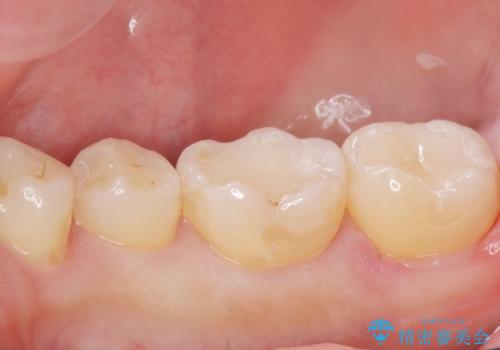

古い樹脂の劣化 セラミックインレー治療

- 保険診療での古い樹脂の劣化が気になるとの事で来院。

二つ樹脂の劣化が見られるので提案をしたが、まずは一つ治療を行いたいとの事でしたので拡大鏡下で劣化した樹脂と虫歯を取り除いた後e-maxインレーにて治療を行いました。

適合の良い詰め物が入りました。

もう一つの治療も現在検討中です。